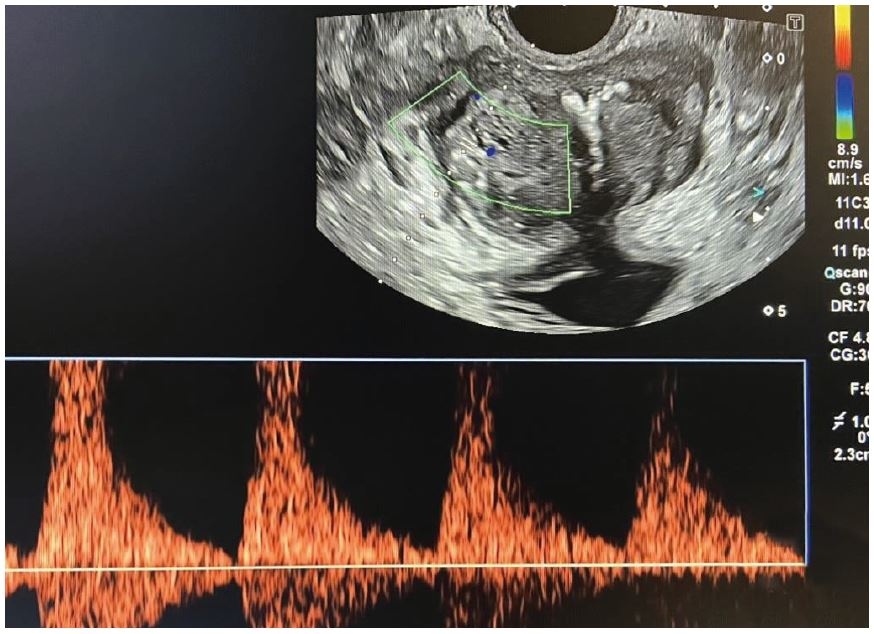

Значення ПСА вище вказаних значень до 10 нг/мл прийнято позначати «сірою зоною», коли важко визначити показання до проведення біопсії ПЗ. Значення ПСА вище 10 нг/мл є основою проведення біопсії ПЗ. Хворому була виконана трансректальна поліфокальна біопсія ПЗ під мультипараметричною (мп) ультразвуковою навігацією та ехоконтрастуванням Соновью (рис. 1 - 5).

Рис. 5. Кольорова та імпульсна доплерографія.